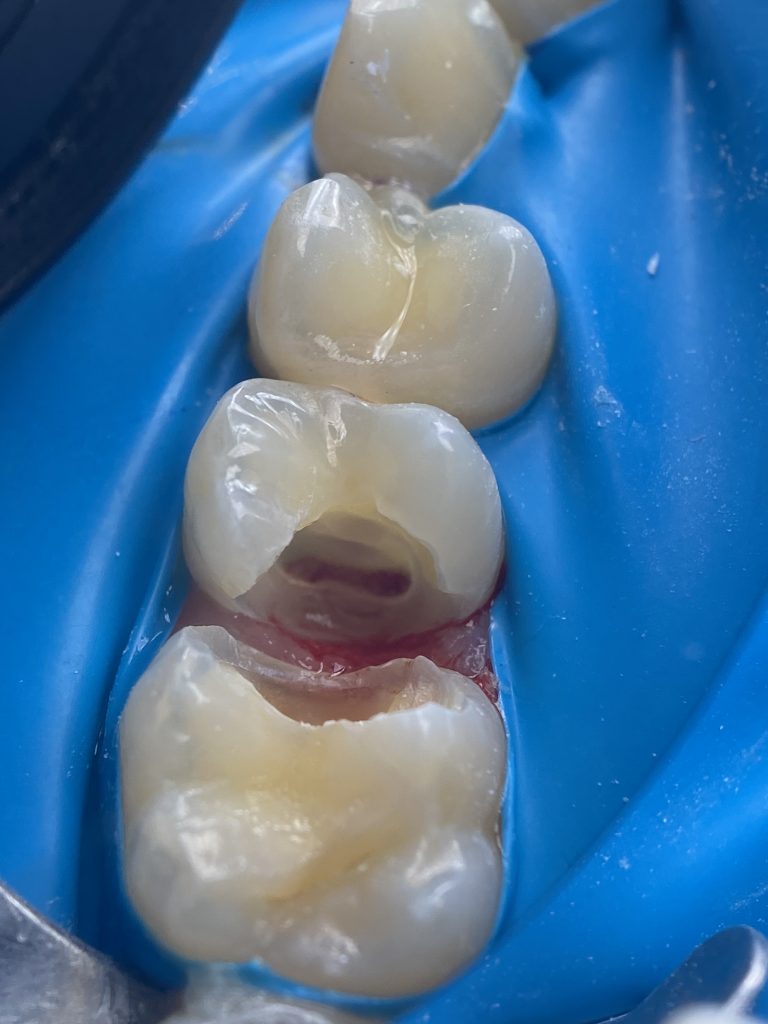

-Coronal pulp removal

-Bleeding control

-MTA application

-Distal wall elevation